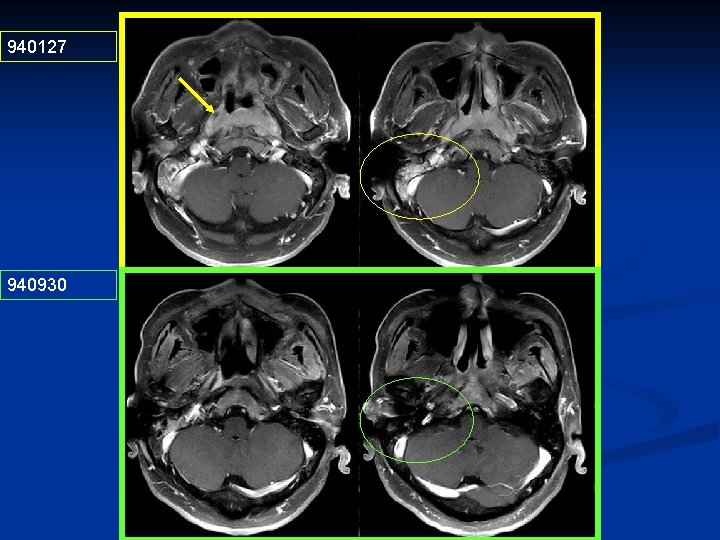

940127 940930